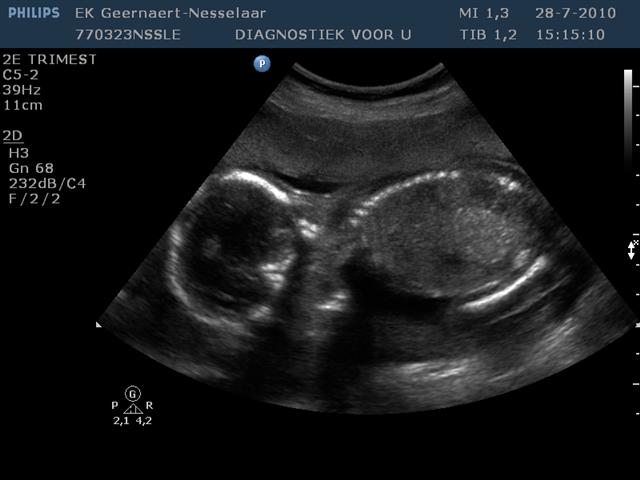

Vanmiddag zijn papa en mama naar Eindhoven geweest voor de 20 weken echo. Best een beetje spannend. Het kindje was wakker en spartelde lekker in het rond. En daar was mama al heel blij mee! De placenta ligt deze keer aan de voorkant, waardoor mama veel minder beweging voelt. Alles is in orde met de kleine! Alles zit erop en eraan, echt ALLES! 10 vingers, 10 teentjes, mooi hoofdje, mooi gevormde orgaantjes, en …. Lucas krijgt dus een broertje! Leuk!! Het leeftijdsverschil is maar zo klein, dat ze heel veel aan elkaar zullen gaan hebben, verwachten we. Mama zal het toch niet kunnen laten, en zal zeker nog wat extra warme jongens winterkleertjes gaan kopen. En natuurlijk wat extra (blauwe) accessoires voor op de babykamer. Nog maar 20 weken wachten en dan is Lucas grote broer!